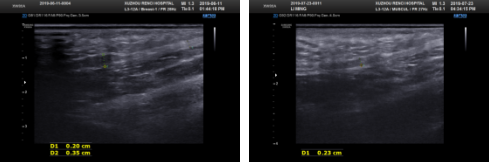

抱着半信半疑的态度,李先生走进了康复医学科,治疗师为他进行了诊治。李先生每周来我院做一次体外冲击波治疗,一个月后疼痛症状减轻,做了5次基本不疼了。刚开始的时候,李先生足底肌腱水肿,测量数值达到0.35cm。经过冲击波治疗5次降低至0.23cm,水肿情况明显改善。

治疗前vs治疗后